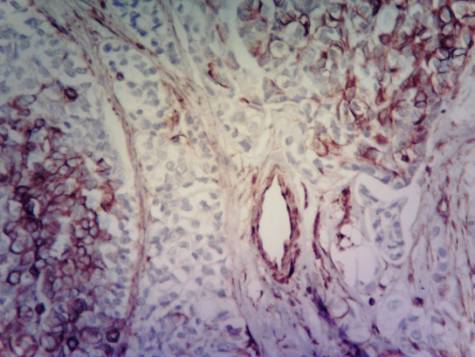

Carcinoma

ductal breast cancer. Tissue around

the tumour. Accumulation of

cells of leukocyte infiltration with different degree of expression.

Immunohistochemical technique for vimentin.